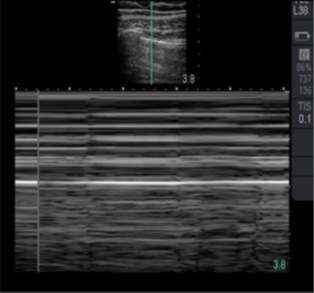

During inspiration and expiration, the visceral pleura back and forth adjacent to the parietal pleural '' moves'' which is known as pulmonary sliding. The hyperechoic bright line represents the junction of the visceral pleural with the parietal pleura, which adheres to the lung as it moves and slides during normal inspiration and expiration, is seen on real-time ultrasound and is a normal finding (Figure 8). The absence of the sliding lung is a direct sign of pneumothorax, but not conclusive, the cardinal sign being the lung point that represents the transition between viable lung and pneumothorax.

Anterior chest

To complete the E–FAST exam, the chest is scanned anteriorly and bilaterally to exclude the presence of pneumothorax and hemothorax. Depending on the patient's body habitus, better resolution is obtained for this evaluation using a high-frequency, shallow-depth linear transducer (10 MHz linear probe) in the case of pneumothorax; and the convex or sector transducer (which have a lower frequency between 3-5 MHz and greater depth) to track hemothorax.

Placement of the linear transducer in the region of the anterior thorax between the 2nd and 3rd intercostal space in the midclavicular line (pneumothorax evaluation).

Both lungs are evaluated for the presence of lung sliding (lung sliding) whose presence rules out the presence of pneumothorax.6 To confirm the diagnosis of pneumothorax by moving the probe both inferiorly and laterally with the notch directed towards the head, looking for the pulmonary point sign that is pathognomonic of pneumothorax, which represents the transition point between the pulmonary parenchyma and air in the pleural cavity (pneumothorax), is seen depicted in B-mode; alternating pulmonary slippage with its absence; and in M mode interspersed as beach and stratosphere signs.

Also in M-mode, look for the beach sign (absent in pneumothorax) and the stratosphere sign found in pneumothorax.

US signs in pneumothorax: absence of pulmonary sliding, pulmonary dot sign, stratosphere sign, or barcode.

US signs that rule out pneumothorax: presence of B lines, presence of pulmonary sliding, beach sign.

In M-mode; Sign of the Beach Blue arrow the waves of the sea: Corresponds to soft parts and in yellow the sand: corresponds to normal lung tissue.

In M-mode; Sign of the Stratosphere or Code of bars, corresponds to pneumothorax.